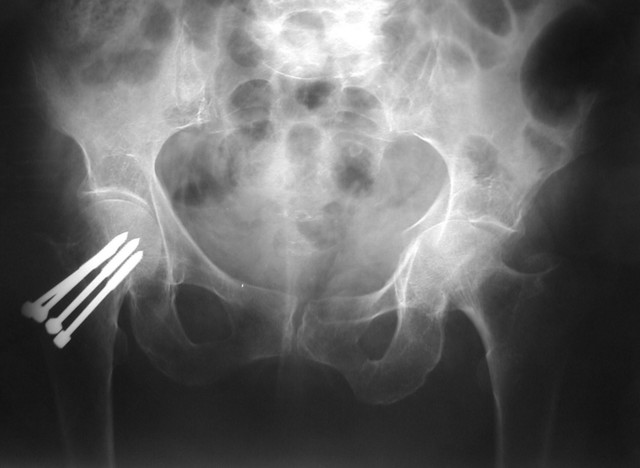

• Fractura Subcapital, lado derecho.

• Tratamiento Osteosintesis con clavos de Knowles

• Hallazgos radiológicas

Fractura transversa con rotura de la lámina cuadrilátera y sub-luxación por protrusión de la cabeza femoral en el interior de la pelvis